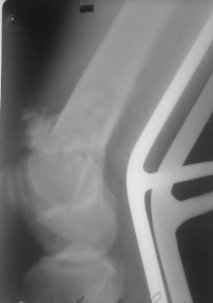

01.12.09г. оперировал больного с подобной травмой в ЦРБ на 4-е сутки после ДТП. Перелом открытый - рана находилась медиально чуть выше надколенника длиной примерно 3-4 см. До этого при поступлении было выполнено ПХО раны и скелетное вытяжение. На момент операции рана без признаков воспаления, состояние больного удовлетворительное.На первичных снимках перелом А3. На операции оказалось С3. Перелом фиксирован мыщелковой пластиной. Для репозиции понадобился медиальный доступ. Медиальный блок дополнен костно-губчатым аутотрансплантатом. На сегодняшний день раны заживают первично, швы еще не сняты, температура тела нормальная, отек бедра значительно уменьшился, имеется анемия средней степени, проводится ЛФК. Фото досылаю